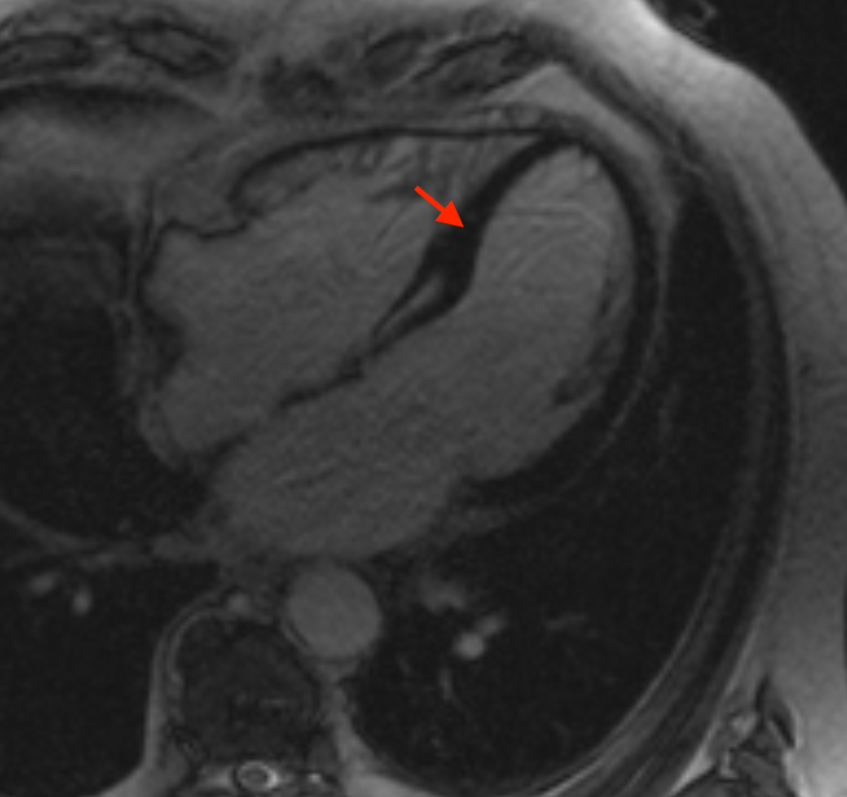

Kαρδιακή μαγνητική τομογραφία (CMR) σε προβολή τεσσάρων κοιλοτήτων, με χρήση σκιαγραφικού (gadolinium) με γραμμική πρόσληψη σκιαγραφικού στο μεσαίο στρώμα του μεσοκοιλιακού διαφράγματος (mid-wall sign). Είναι χαρακτηριστικό για ιδιοπαθή διατατική μυοκαρδιοπάθεια